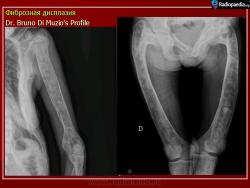

Локализация: для монооссальной фиброзной дисплазии характерно поражение одной из костей лицевого черепа, а также бедренной или большеберцовой кости, реже одного ребра; при полиоссальной фиброзной дисплазии страдают в первую очередь бедренная, большеберцовая и тазовые кости, не исключено и поражение мелких костей стопы, черепа, реже ребер. Рентгенологическая картина фиброзной дисплазии разнообразна. Патологические участки могут быть то более плотными, то более прозрачными по сравнению с окружающей костью, иногда имеют вид «матового стекла». Одни очаги четко отграничены зоной склероза, контуры других расплывчатые, что особенно характерно для костей черепа. Нередко выявляются узуры в кортикальном слое, а при наличии перелома — отчетливая периостальная реакция. При макроскопическом исследовании определяются беловато-красные опухолевые очаги разной плотности, в зависимости от степени выраженности их минерализации. Имеются многочисленные кисты, заполненные желтоватой или красноватой жидкостью, и полупрозрачные участки хряща до 3 см в диаметре.

Полиостотическая фиброзная дисплазия у пациента с синдромом Маккьюн - Олбрайта.